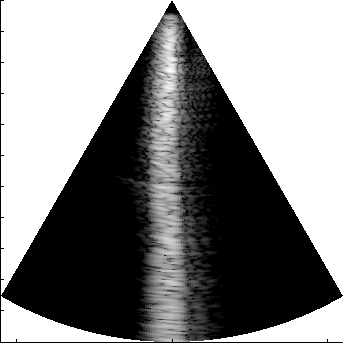

Verasonics_P2-4_parasternal_long_small.uff

examples: FI phased array, minimal_example